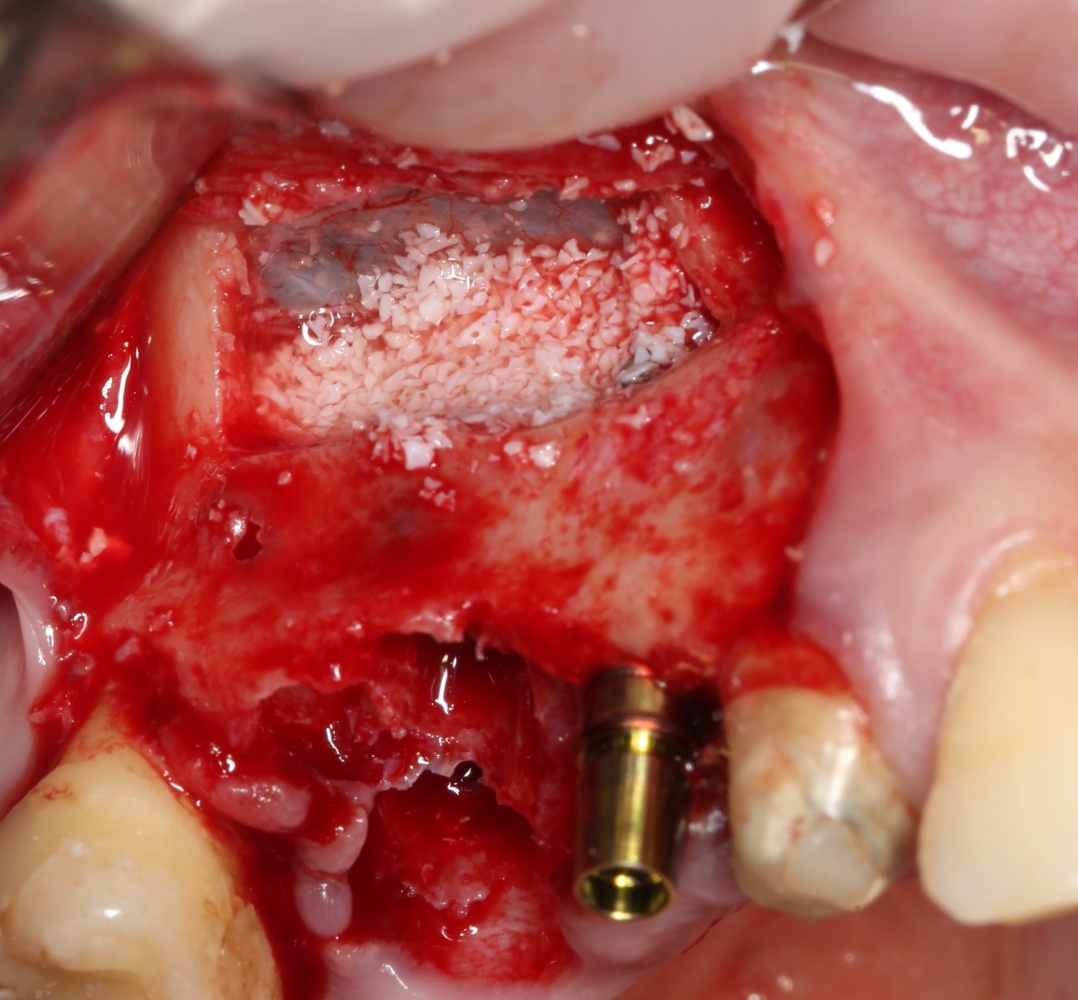

Кстати, обрати внимание на ширину альвеолярного гребня (левая картинка). Она чуть меньше 3 мм. Это объясняет, почему я засомневался в возможности установки имплантатов одновременно с остеопластикой. Понятно и без КЛКТ.

Возвращаемся к основной операционной области. Еще раз посмотрим на альвеолярный гребень, поофигеваем от его ширины и моих грандиозных планов:

Я зафиксировал костный блок практически без адаптации на несколько винтов. Обрати внимание, что винты находятся в зоне, где не планируется установка имплантатов. Фиксация должна быть надежной, поскольку мне еще предстояла подготовка лунок для имплантатов. Трех винтов для этого вполне достаточно.

Глянем на то, что получилось:

Конкретно в этом клиническом случае между костным аутотрансплантатом, ложем и имплантатами есть пустое пространство. Если его не изолировать от мягких тканей, они прорастут и осложнят интеграцию аутографта. Поэтому я решил перекрыть костный блок барьерной мембраной, пусть это делает хирургическую операцию немного дороже.